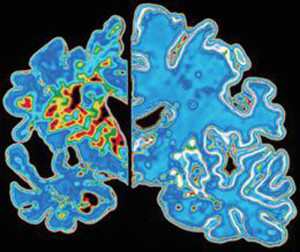

L’ESPERIMENTO. Nello studio, finanziato dal Medical Research Council e pubblicato su Nature, i ricercatori hanno osservato gli effetti del letargo sui due gruppi di topi, sani e con malattia di Alzheimer.Dopo 45 minuti di ipotermia a 16-18 gradi, al ripristino della temperatura fisiologica, la proteina è entrata in funzione nei soli topi sani e non nei malati, con conseguente mancato ripristino delle sinapsi al “risveglio”. Inoltre, la degenerazione dei neuroni tipica della malattia appare più accelerata tanto più basso il livello di RMB3.

L’IPOTERMIA CEREBRALE. L’abbassamento della temperatura corporea è utilizzato da tempo a scopo terapeutico sui pazienti con trauma cranico che vengono tenuti in coma e ipotermia proprio per mettere il cervello al riparo da ulteriori danni. Infatti, il trattamento dell’ipotermia cerebrale indotta in modo controllato, in altre parole il raffreddamento progressivo del paziente, permette di proteggere il cervello, rallentandone il metabolismo e quindi diminuendo la quantità di glucosio e di ossigeno consumato. Lo stato di torpore permette di risparmiare energia, dando tempo all’edema che segue il trauma cranico di riassorbirsi.